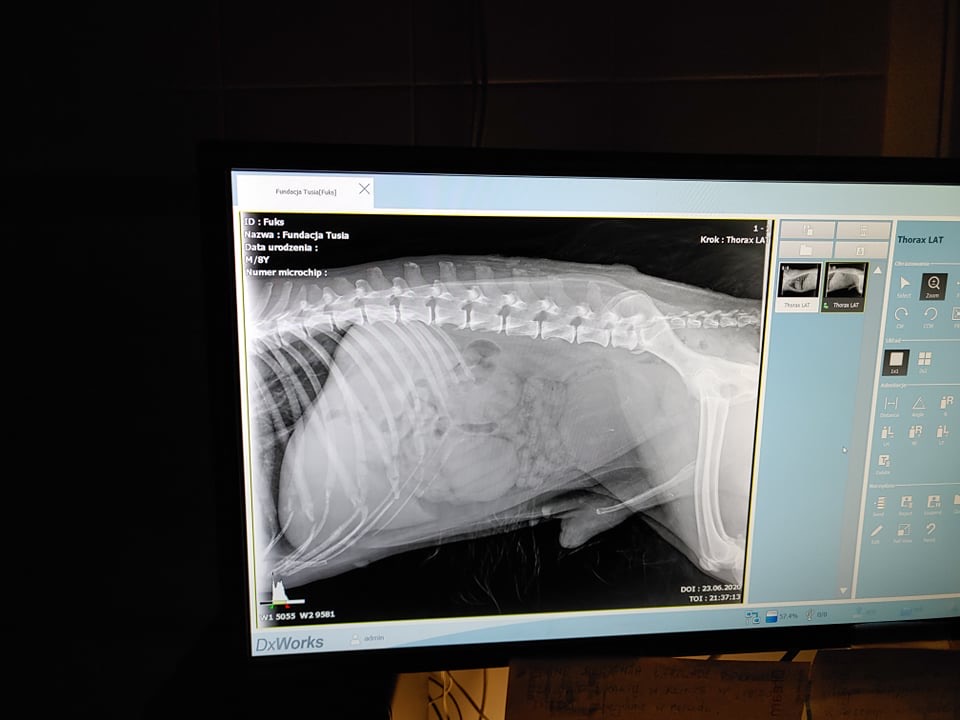

#AKTUALIZACJA IV: Jan K. – „Fuks jest w tej chwili diagnozowany, miał zrobione badania RTG, USG i badanie krwi. Dostał silne leki przeciwbólowe i śpi. Czekamy na opinię chirurga.”

AKTUALIZACJA VIII: Fundacja – Fuks już w klinice w Auxilium. Stan ciężki, rokowania ostrożne. Został obejrzany przez lekarzy, wykonano dodatkowe rtg. Czaszka pogruchotana, możliwe że odłamki wbiły się w zatoki, ropno- krwisty wysięk z nosa, oczy zapadnięte, krwiaki w pyszczku, brzuch tkliwy. W tej chwili zajmują się nim w szpitalu. Jutro rano bad krwi i będzie go oglądał dr Olkowski. W zależności od wyników i jego stanu, podjęte zostaną kolejne kroki diagnostyki i leczenia. Dołączam również zdjęcia, trzymajcie kciuki, będziemy was informować na bieżąco.

Stan Fuksa jest bardzo ciężki, czaszka zgruchotana, obrzęk, ropno-krwisty wysięk z nosa, wyschnięte, zapadnięte gałki, krew w uszach, krwiaki w pyszczku.

W USG (skrót, cały opis w karcie poniżej) – wątroba niepowiększona, pęcherzy żółciowy w normie, śledziona niepowiększona, nerki miąższ lekko niejednorodny, łagodnie podwyższona echogeniczność kory, miedniczki i moczowody nieposzerzone, nadnercze prawe o niejednorodnym miąższu z nielicznymi punktowymi echami w typie mineralizacji/zwłóknień, trzustka i żołądek adekwatnie do wieku i „diety”, prostata o przewlekłej przebudowie, możliwe że pozapalnej, w śródbrzuszu obecna masa w postaci regularnego owalnego guza (guz rozrostowy nowotworowy? jądro wnętrowskie?), węzły chłonne biodrowe po stronie prawej w przewadze przebudowane, naciekowo- rozrostowo, hipoechogeniczne i niejednorodne, obecne punktowe mineralizacje. Wskazane badanie bipsyjne.

Fuks cały czas dostaje antybiotyk, silne leki przeciwbólowe, płyny. Jego stan jest stabilny, ale nie na tyle dobry, by mógł przejść kolejne badania, kolejne poważniejsze badania obrazowe najwcześniej w piątek.